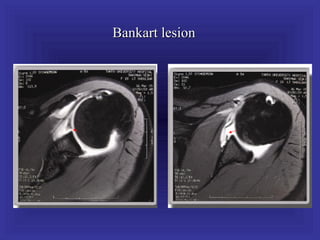

Bankart lesion